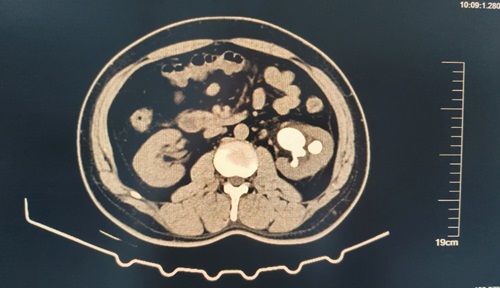

术后带输尿管支架管1个月对比图:

由CT可见:患者左侧肾盂输尿管支架术后改变,较术前左肾结石体积基本消失,原左侧输尿管上段结石、左肾盂-输尿管结合部扩张较前未见。